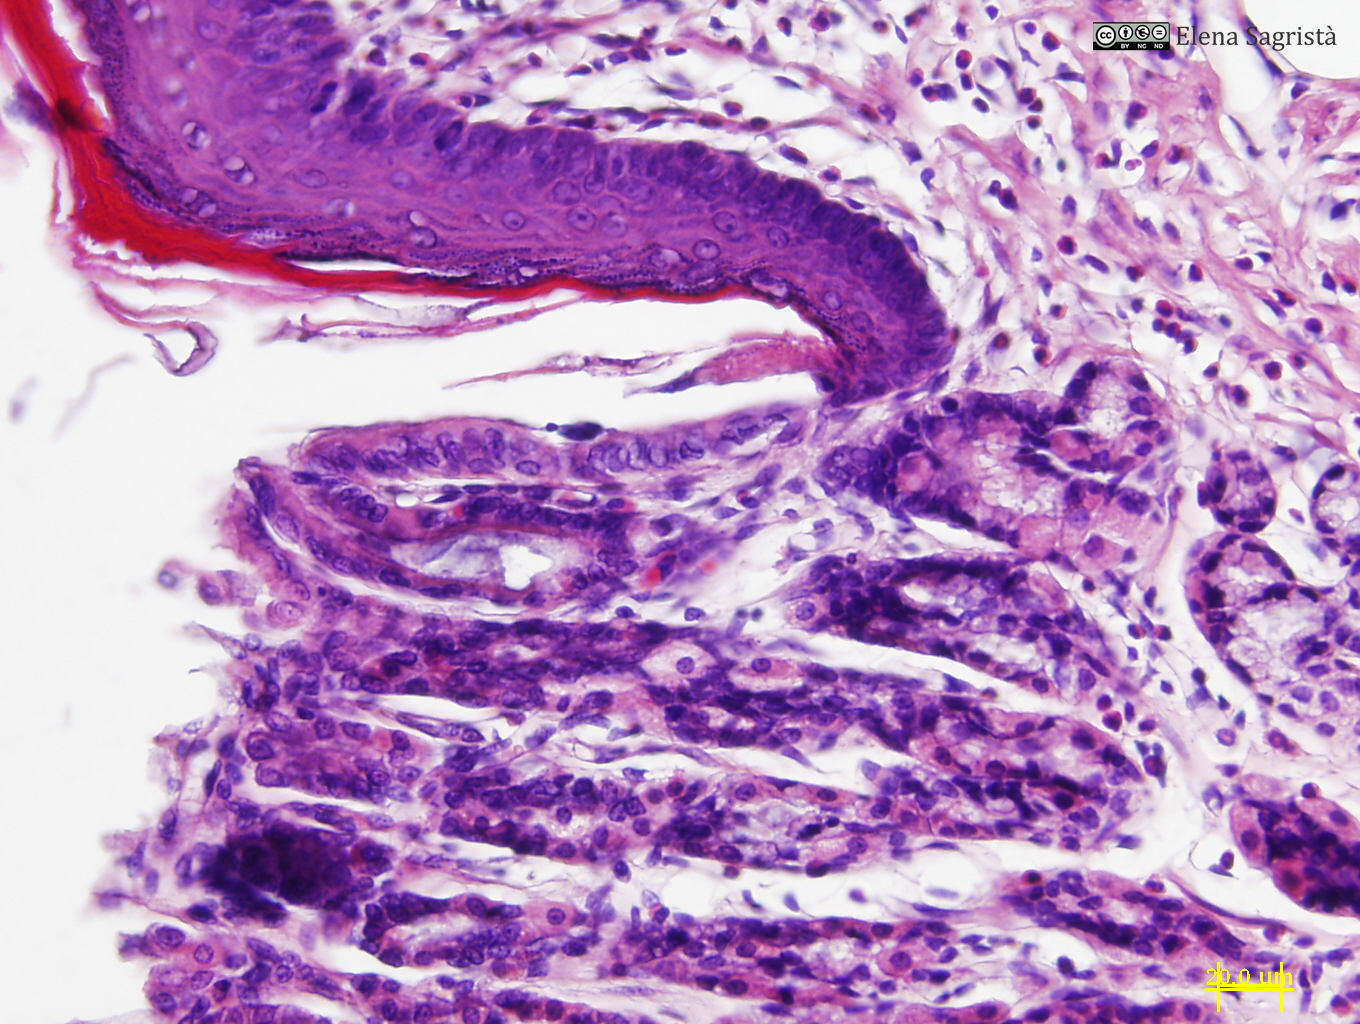

Histologia imatges: 16 Estòmac

Imatges de preparacions histològiques d'Estómac. Microscopia òptica.